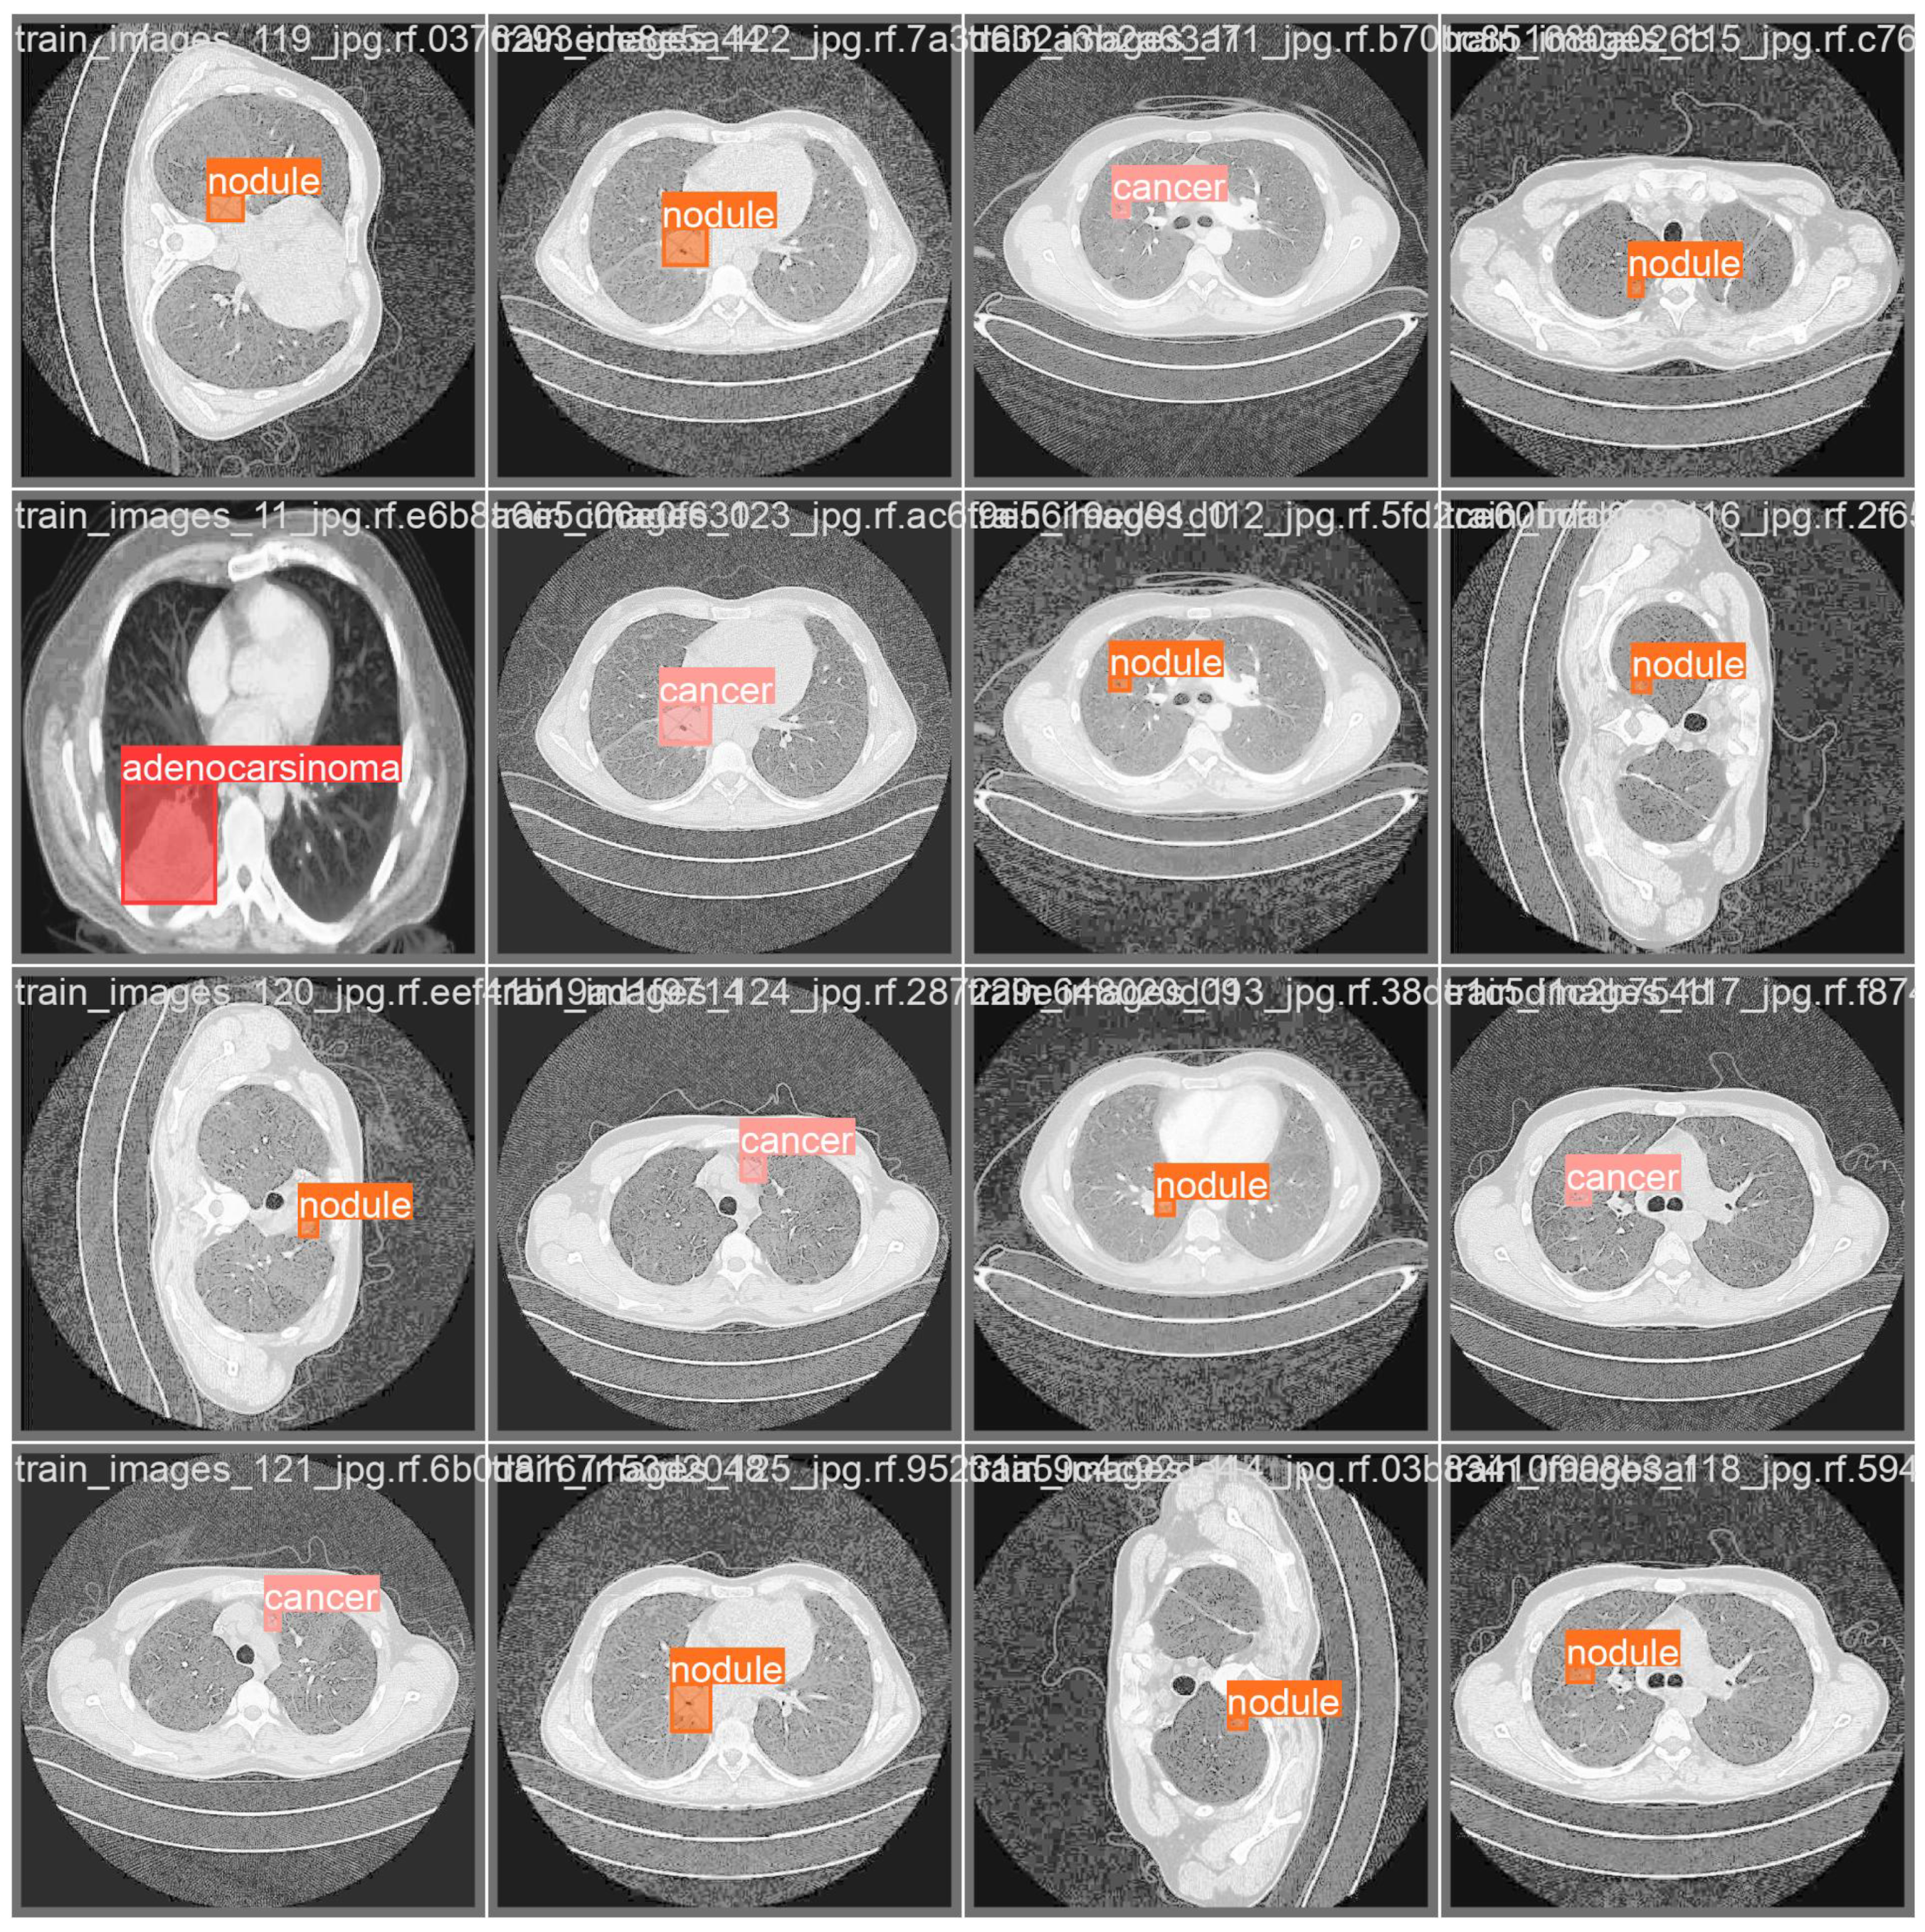

- Adenocarcinoma (Blue Line):

- -

- The blue line represents the precision–recall relationship for the adenocarcinoma class.

- With an average precision (AP) of 0.734, the model performs relatively well in detecting adenocarcinoma, maintaining high precision and recall values.

- Cancer (Orange Line):

- The orange line represents the performance for the cancer class.

- An AP of 0.588 indicates moderate performance, with a noticeable drop in precision as recall increases, suggesting that the model struggles more with this class compared to adenocarcinoma and nodules.

- Nodule (Green Line):

- The green line shows the precision–recall for nodules.

- With the highest AP of 0.802, the model performs best on this class, indicating high precision and recall across most thresholds.

- All Classes (Bold Blue Line):

- The bold blue line represents the overall performance across all classes, with an mAP@0.5 of 0.708.

- The mean average precision (mAP) at an IoU threshold of 0.5 provides a single metric summarizing the model’s performance across all classes.

- An mAP@0.5 of 0.708 suggests that the model has a strong overall detection capability, balancing precision and recall well.

| Class | Image | Instances | Box (P) | Box (R) | Box (mAP50) | Box (mAP50-95) |

|---|---|---|---|---|---|---|

| all | 324 | 332 | 0.757 | 0.738 | 0.71 | 0.488 |

| adenocarsinoma | 324 | 45 | 0.815 | 0.685 | 0.713 | 0.492 |

| cancer | 324 | 46 | 0.572 | 0.783 | 0.588 | 0.467 |

| nodule | 324 | 241 | 0.884 | 0.747 | 0.831 | 0.505 |

| Class | Image | Instances | M (P) | M (R) | M (mAP50) | M (mAP50-95) |

| all | 324 | 332 | 0.75 | 0.733 | 0.708 | 0.438 |

| adenocarsinoma | 324 | 45 | 0.815 | 0.685 | 0.734 | 0.539 |

| cancer | 324 | 46 | 0.572 | 0.783 | 0.588 | 0.366 |

| nodule | 324 | 241 | 0.865 | 0.73 | 0.802 | 0.41 |